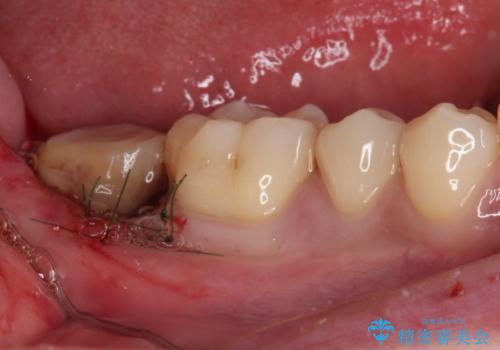

銀歯の頃は頻繁に外れていたため、不快感が強かったようですが、歯冠長を延長したことで外れにくいクラウンを装着することができ、不快感が改善されました。